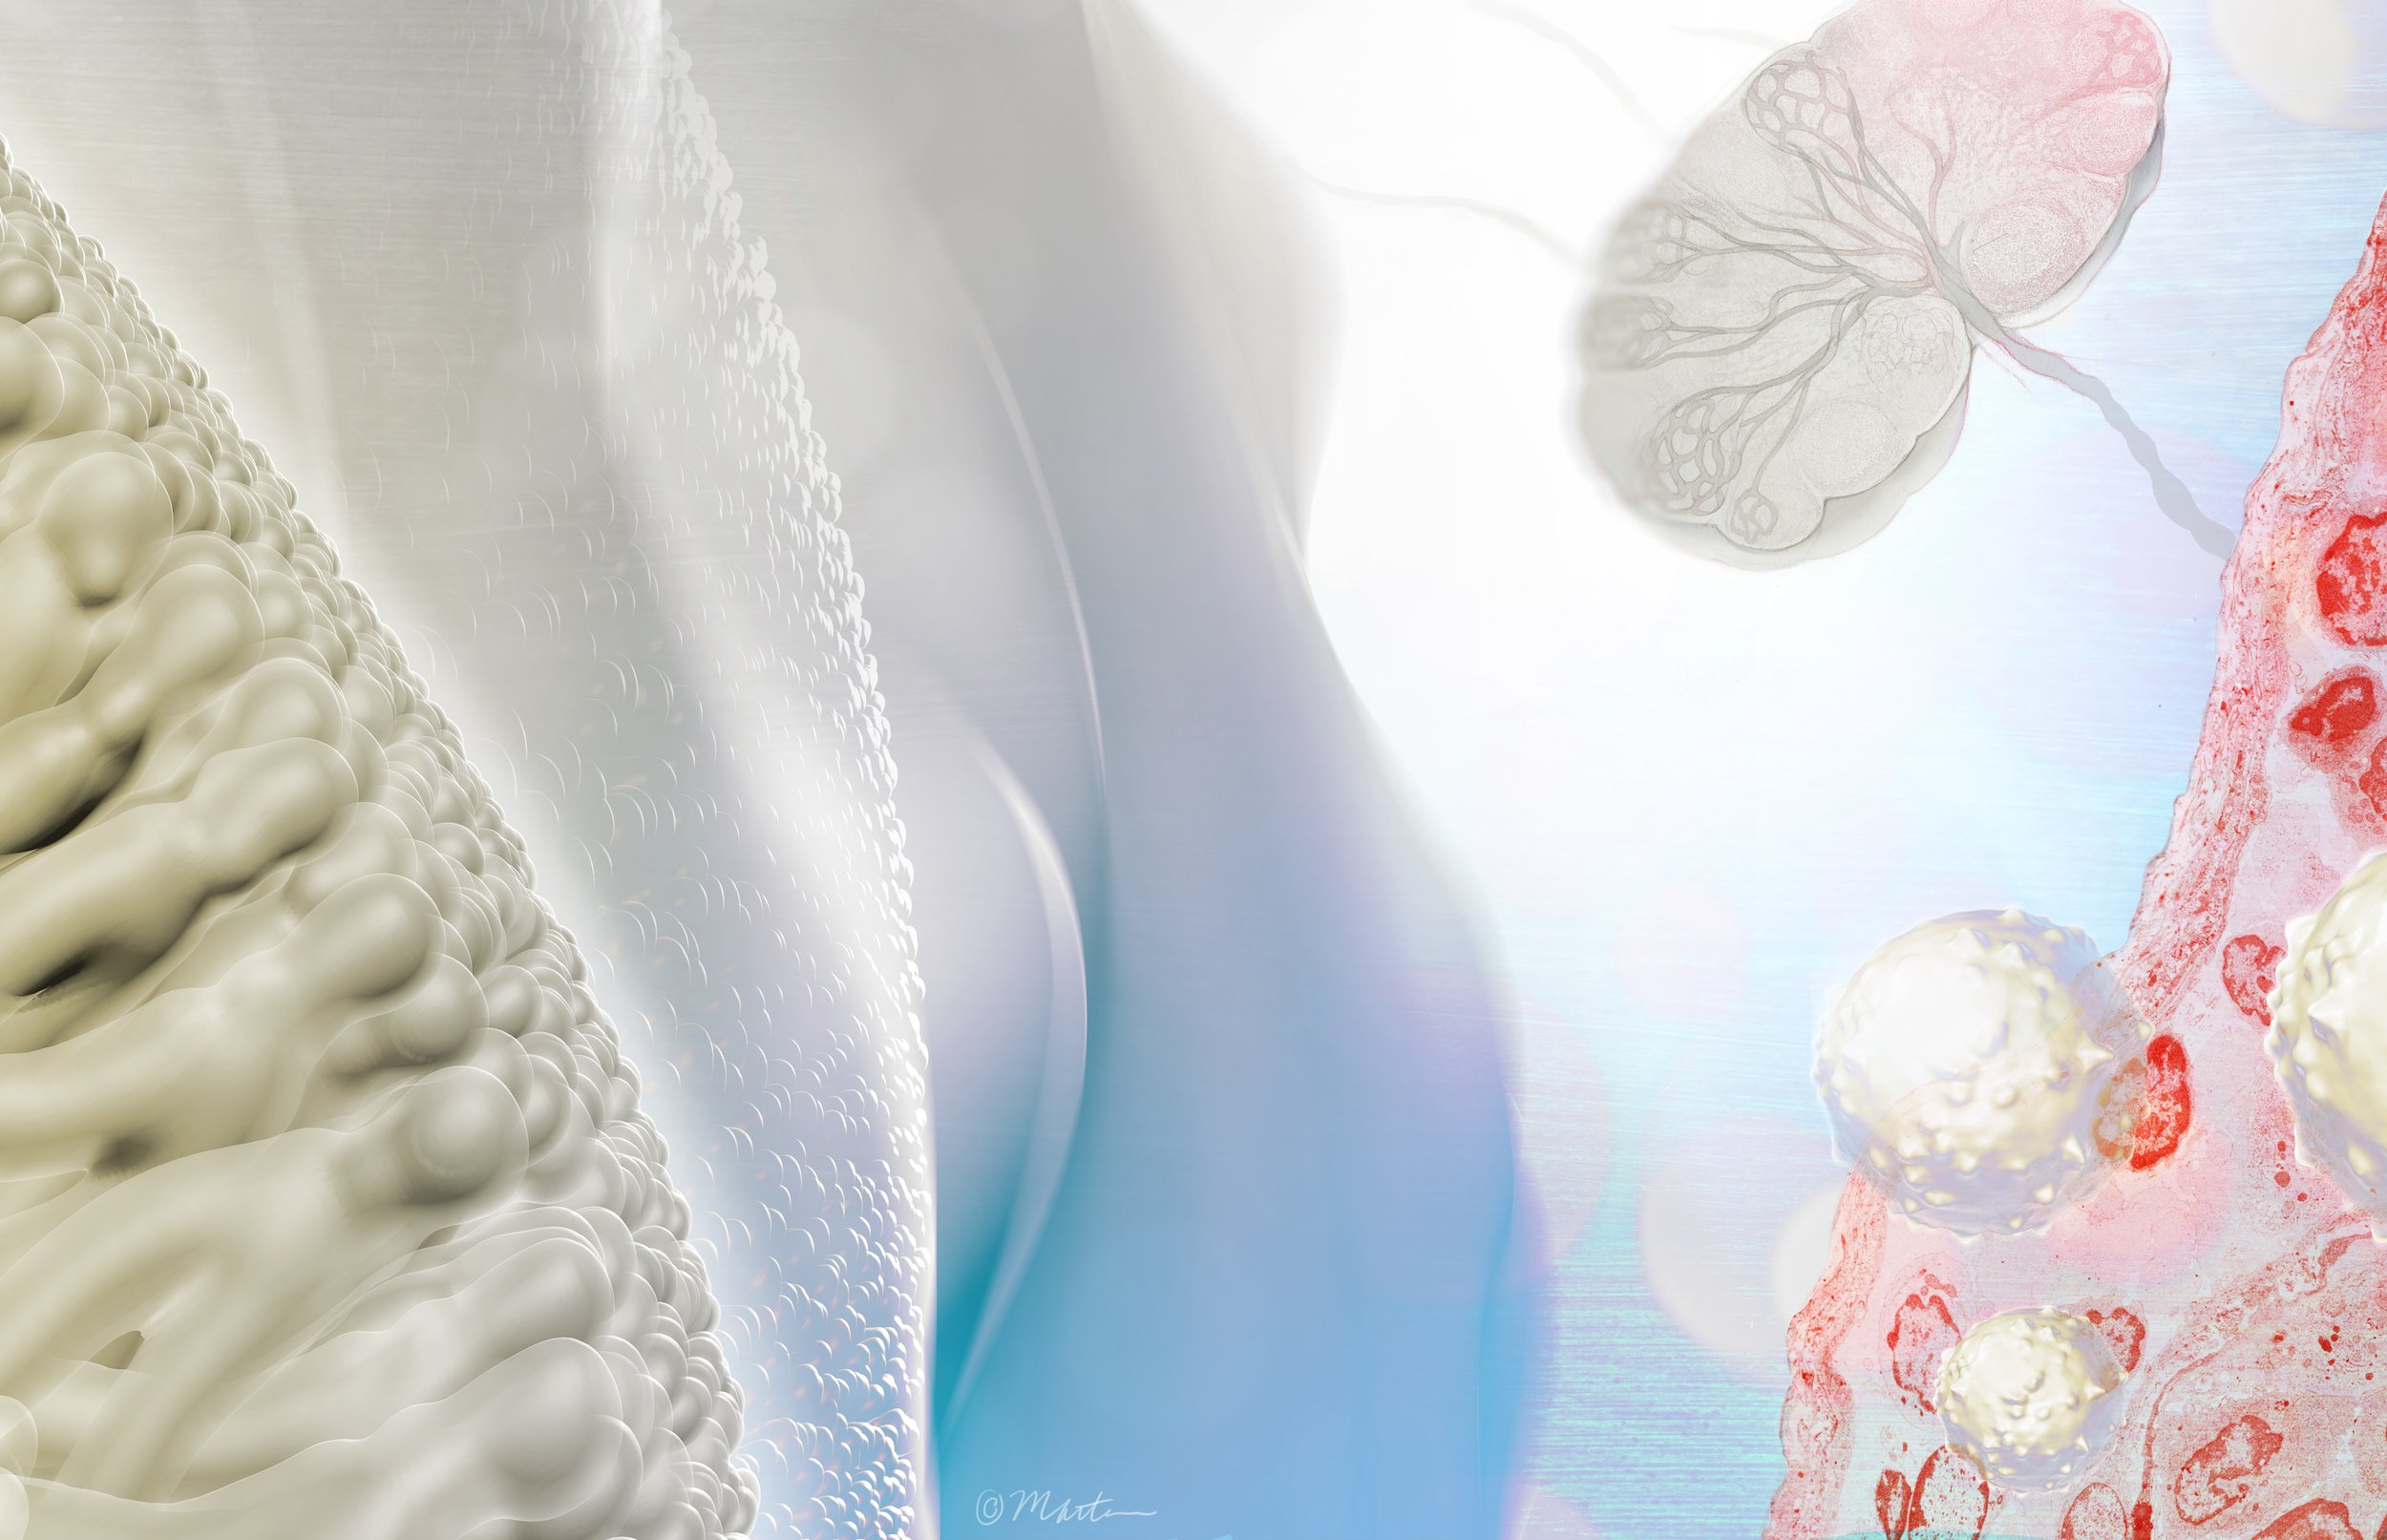

Vaginal Atrophy